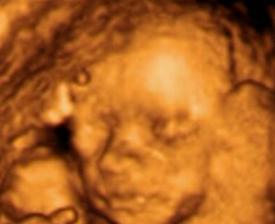

Ultrazvuky a bruska

krasne 4D fotky 🙂